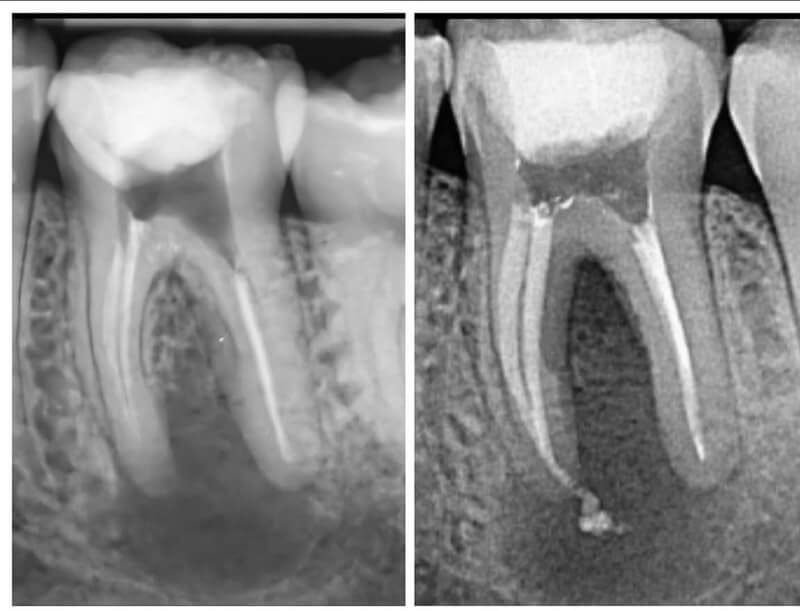

Endodonția este o ramură esențială a stomatologiei, axată pe diagnosticarea, prevenirea și tratamentul afecțiunilor pulpei dentare și a țesuturilor periapicale. Această specialitate joacă un rol crucial în salvarea dinților naturali, evitând extracțiile și menținând sănătatea orală pe termen lung. Prin tehnici avansate și echipamente de ultimă generație, endodonția asigură tratamente precise și eficiente, contribuind la redarea sănătății și funcționalității dinților într-un mod durabil și predictibil.

Utilizarea tehnicilor moderne asigură un tratament rapid, precis și confortabil pentru pacient.

Reconstituirea coronară cu materiale de calitate conferă rezistență pe termen lung.